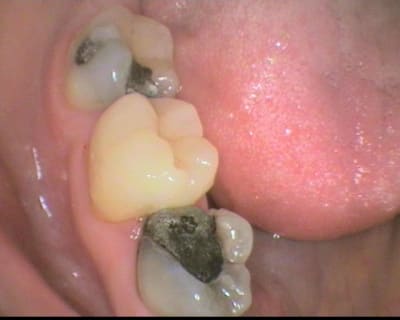

Steph, je suis aussi fou que toi, la preuve:

L'onlay composite 7/8 de la 27 a tenu 9 ans sans problème et la patiente a même mastiqué dessus pendant 5 années alors que la 26 a du être extraite! J'ai du le remplacer en la taillant par un inlaycore lorsque la paroi restante commençait à se carier en palatin et ai réaliser alors enfin un bridge...

L'onlay de la 16 posé en même temps est toujours en place après 14 ans malgré ses parois fines. Où se situent véritablement les limites?

Désolé pour la qualité des photos, mais à cette époque je n'avais que ma vieille caméra endobuccale à fibre optique.

les plâtres ont été conservés comme modèles de montre depuis et m'ont servi à convaincre de nombreux patients de l'intérêt des onlays, comme quoi un brin de folie de temps en temps cela peut faire du bien ;o) ...